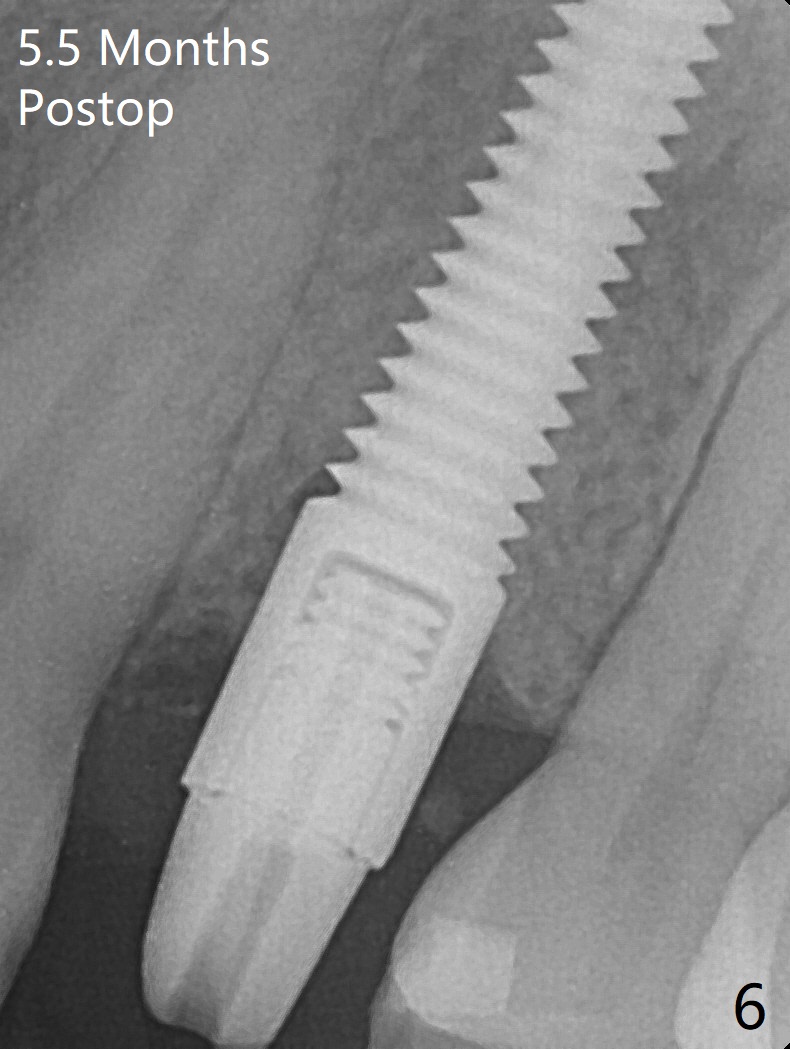

Since there is no buccal plate atrophy at 4, or 8, socket shield is not attempted at #31. Extraction turns out to be difficult because of tooth fracture. The buccal and palatal flaps have to be elevated minimally for tooth sectioning and purchase point formation. More surprising, a 4.5 mm implant appears to be too wide for the space; a 4x17 mm implant achieves insertion torque >60 Ncm (Fig.1,2). In fact Vanilla graft is placed before and after implantation. The advantage of bone graft before implant is that the graft is able to be placed as apical as possible to repair the apical defect if it is present. The disadvantage is hemorrhage. After placement of a 3.5x5 mm abutment, an immediate provisional is fabricated (Fig.3 P), which seems to be able to hold the separated buccal papillae in place. The latter heal around the immediate provisional 9 days postop (Fig.4). Because of the seal, the bone graft remains in place 1 month postop (Fig.5). There is no bone loss 5.5 months postop (Fig.6,7) or 6.5 months postop (immediately post cementation, Fig.8).